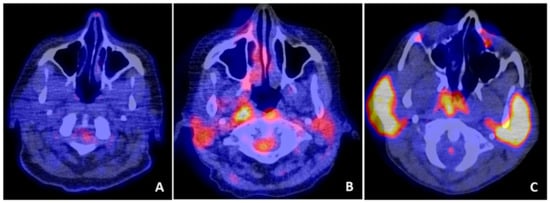

- Cohen, C.; Mekinian, A.; Uzunhan, Y.; Fauchais, A.L.; Dhote, R.; Pop, G.; Eder, V.; Nunes, H.; Brillet, P.Y.; Valeyre, D.; et al. 18F-fluorodeoxyglucose positron emission tomography/computer tomography as an objective tool for assessing disease activity in Sjögren’s syndrome. Autoimmun. Rev. 2013, 12, 1109–1114. [Google Scholar] [CrossRef]

- Keraen, J.; Blanc, E.; Besson, F.L.; Leguern, V.; Meyer, C.; Henry, J.; Belkhir, R.; Nocturne, G.; Mariette, X.; Seror, R. Usefulness of 18F-Labeled Fluorodeoxyglucose–Positron Emission Tomography for the Diagnosis of Lymphoma in Primary Sjögren’s Syndrome. Arthritis Rheumatol. 2019, 71, 1147–1157. [Google Scholar] [CrossRef]